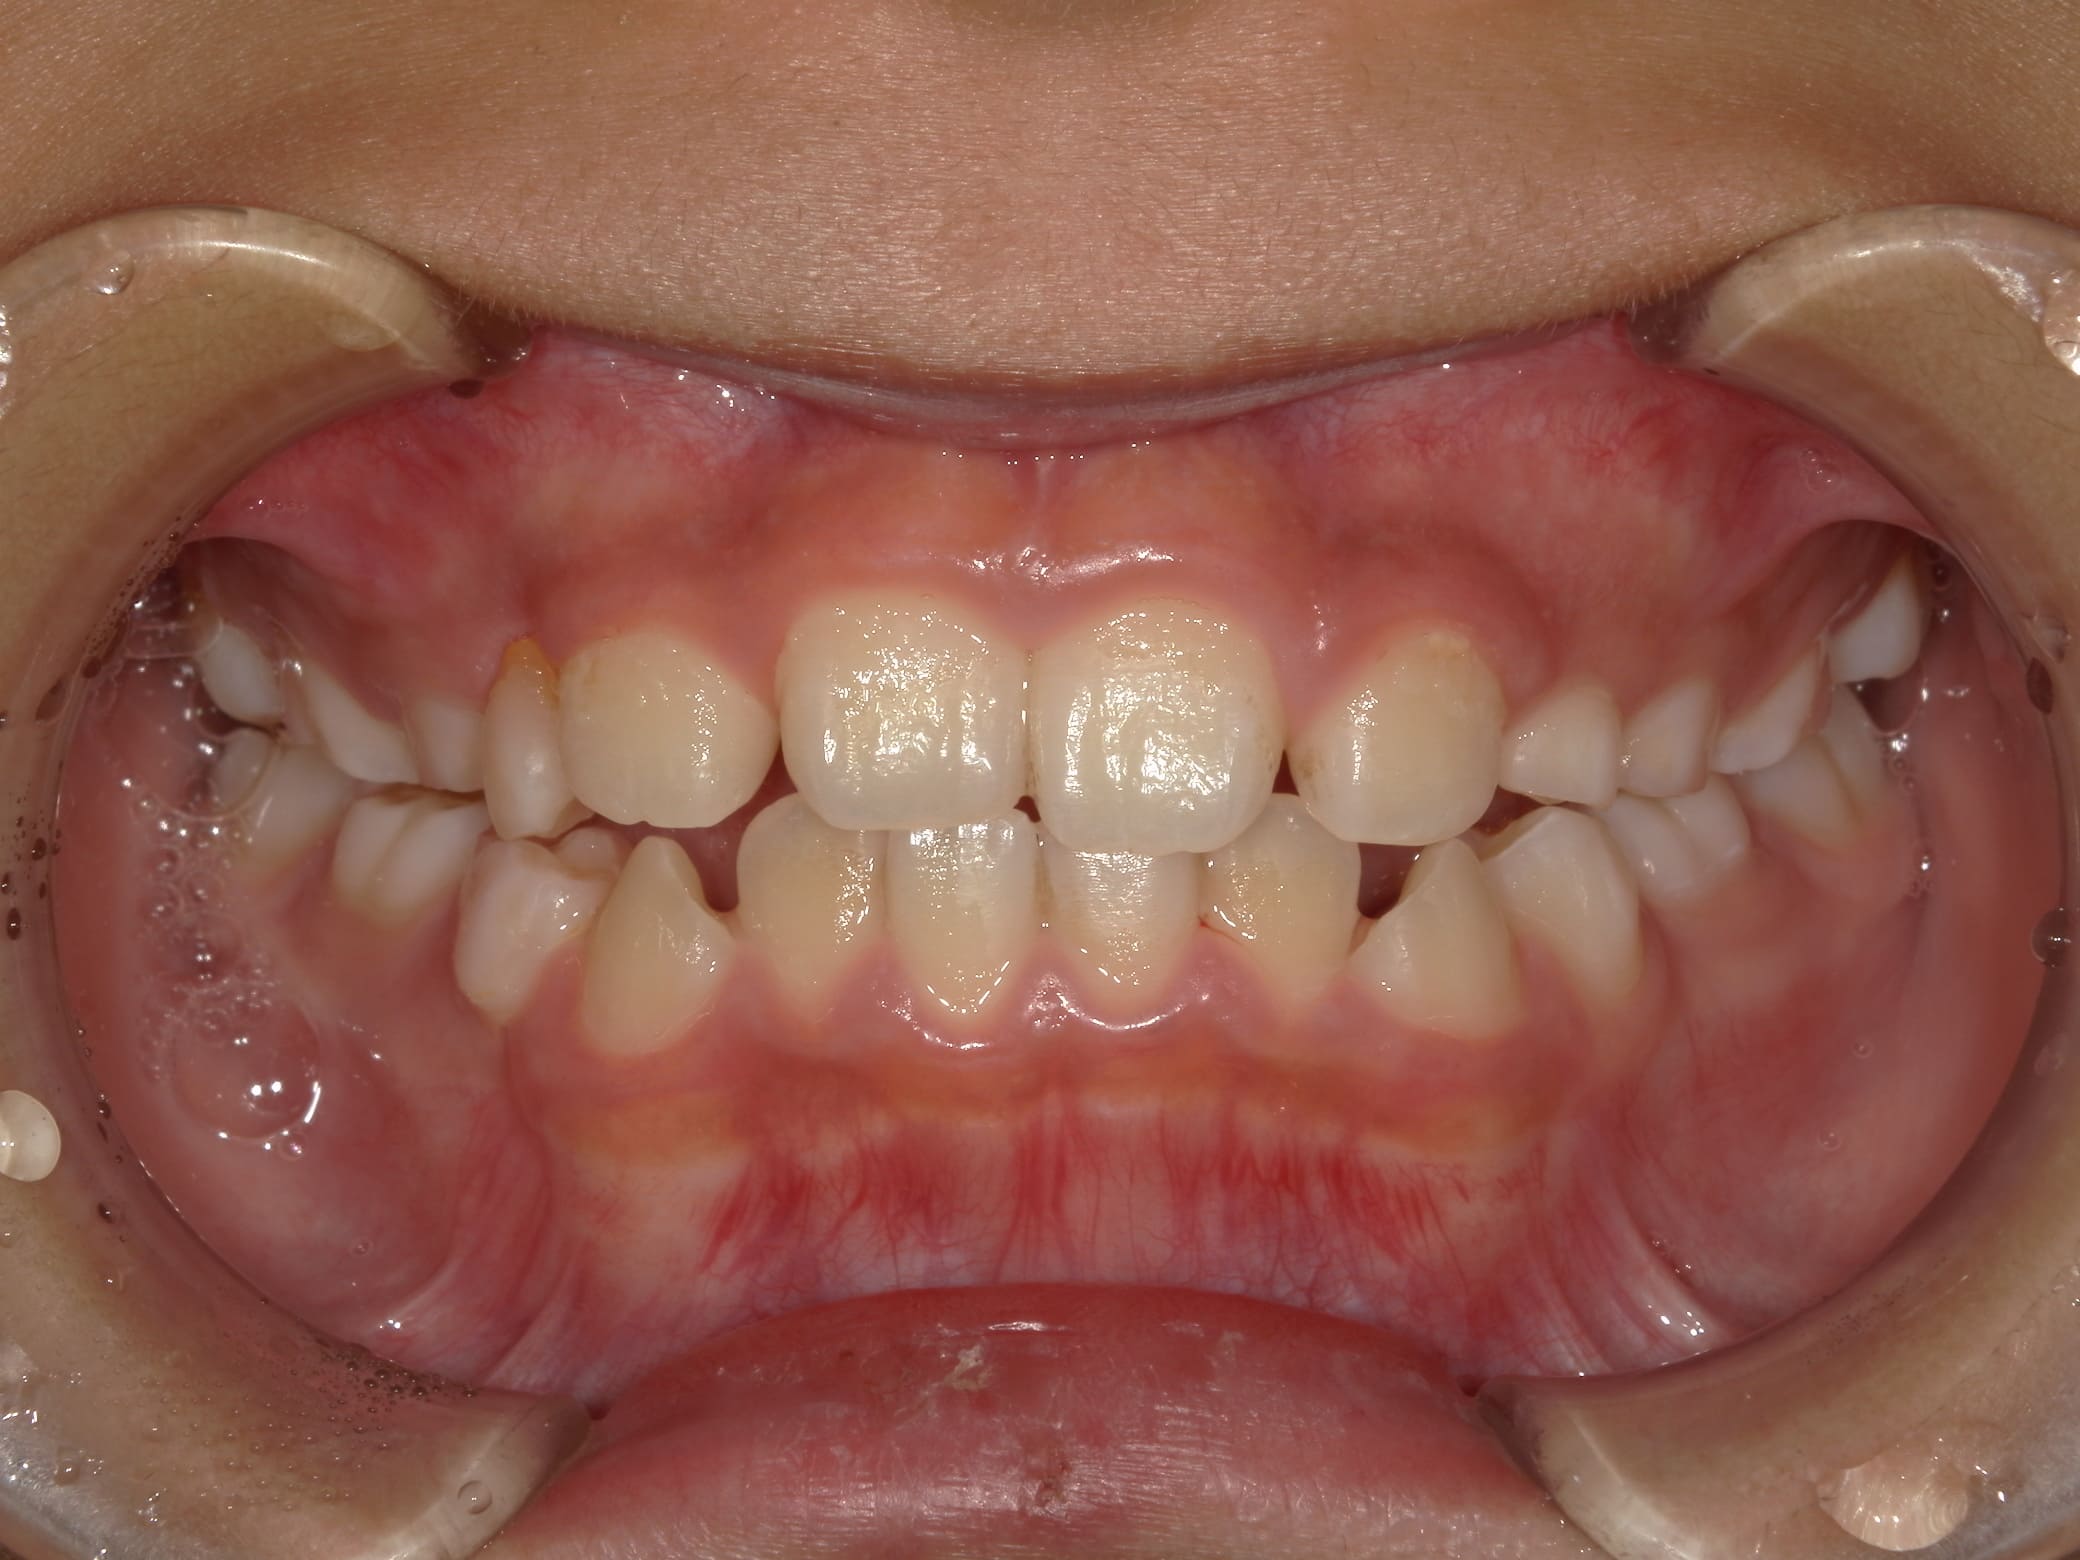

| 年齢・性別 | 8歳9ヶ月の男児 |

|---|---|

| 主訴 | 前歯の咬み合わせが逆になっており、歯根や歯肉への影響を懸念されて来院された患者様です。 |

| 治療期間・回数 | 3年7ヶ月・20回 |

| 費用 | 460,000円(税別) |